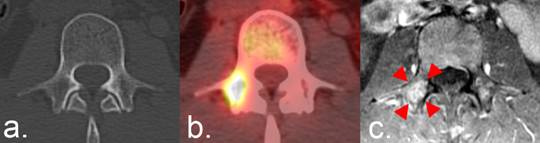

Figure 2

Use of FDG PET/CT according to the RECIST 1.1 criteria. (a) CT of the L3 vertebra in a patient with breast cancer reveals no indication of bone metastases. (b) Focal FDG uptake indicative of metastatic disease is present on PET/CT. The interval development of an FDG-avid focus, in the absence of any other indication of disease progression, is considered progressive disease under RECIST 1.1 unless it corresponds to a pre-existing, anatomically stable abnormality. RECIST 1.1 specifies that the metastasis is to be confirmed on a follow-up CT.(c) A fat-saturated T1-weighted axial MRI image obtained following the administration of intravenous contrast was available and reveals an enhancing lesion in the location of FDG uptake (arrowheads), confirming the presence of the metastasis.